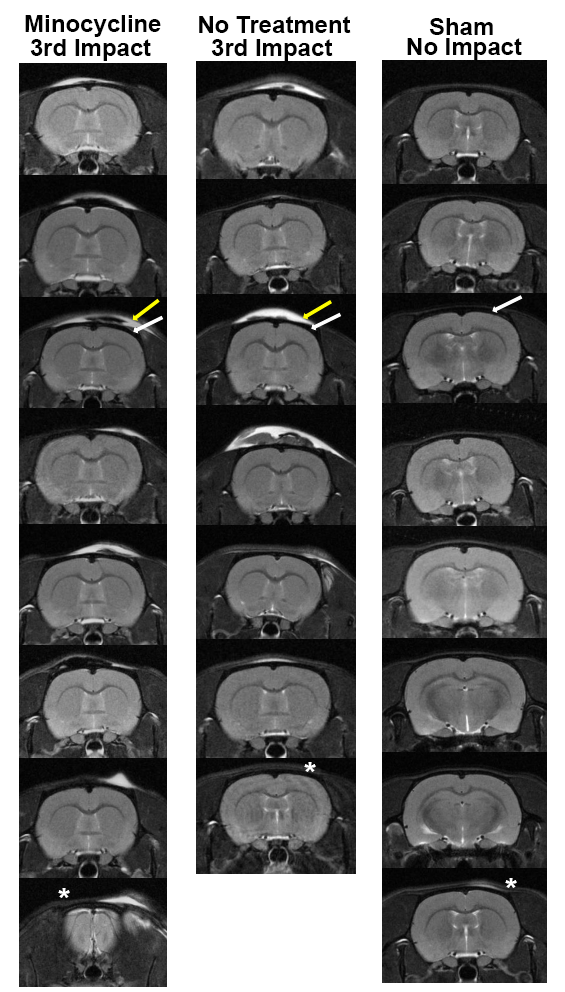

Figure 1. Neuroradiology. Shown are radiograms of each subject in each experimental group. The edema (yellow arrow) that appears on the skin and tissue overlying the skull (dark area noted by white arrow) appears white using a T2 weighted pulse sequence.

Shown are radiograms of each subject in each experimental group. The edema (yellow arrow) that appears on the skin and tissue overlying the skull (dark area noted by white arrow) appears white using a T2 weighted pulse sequence. One rat in the no treatment impact group did not present with edema at the putative site of impact (see asterisk). In all other cases the impact site and edema at the forebrain (level of Bregma) was consistent across all rats following the 3rd impact except for the last rat in the minocycline treated group where the impact sited is more rostral near the cerebrum (see asterisk). While all sham rats had no hits, one showed some evidence of edema that could not be accounted for (see asterisk).